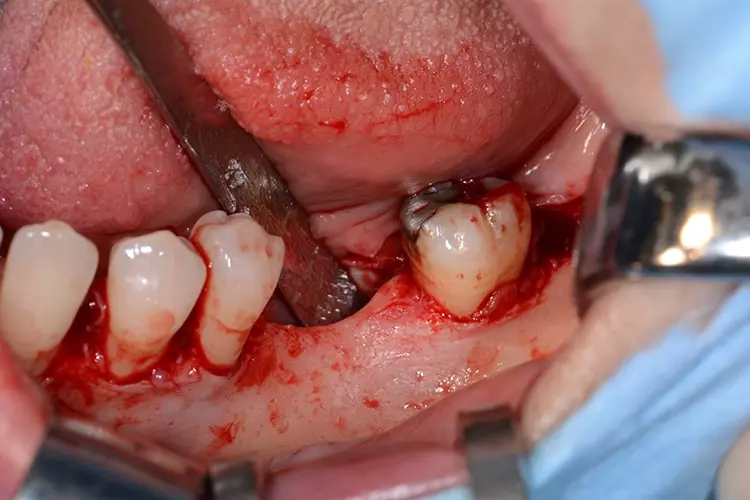

Eine 53-jährige gesunde Patientin stellte sich in unserer Klinik zur prothetischen Rehabilitation bei Vorliegen einer bilateralen Schaltlücke bei fehlenden Zähnen 37 und 36 vor. Zum Zeitpunkt der Erstvorstellung zeigte sich ein prothetisch und konservativ insuffizient versorgtes Gebiss mit einer Freiendsituation in regio 17 und 16 sowie Schaltlücken in den Regionen 37 und 36 sowie 46 und 47 (Abb. 1). Zur Beurteilung der radiologischen Ausgangssituation wurde präoperativ eine Digitale Volumentomographie angefertigt.

Unter Berücksichtigung der klinischen und radiologischen Ausgangssituation sollte im Vorfeld eine indikationsbezogene Behandlung geplant werden. Bei Vorliegen eines nach apikal schmal verlaufenden alveolären Kieferkamms, was eine horizontale Augmentation von mehr als 3 mm voraussetzt, ist ein simultanes Verfahren mit Knochenaugmentation und zeitgleiche Implantation nicht erfolgversprechend [6,7]. Folglich sollte in Anbetracht der Empfehlung der S2k-Leitlinie „Implantologische Indikationen für die Anwendung von Knochenersatzmaterialien“ bei komplexen Defekten die Implantation sekundär als zweizeitiges Vorgehen erfolgen [3].